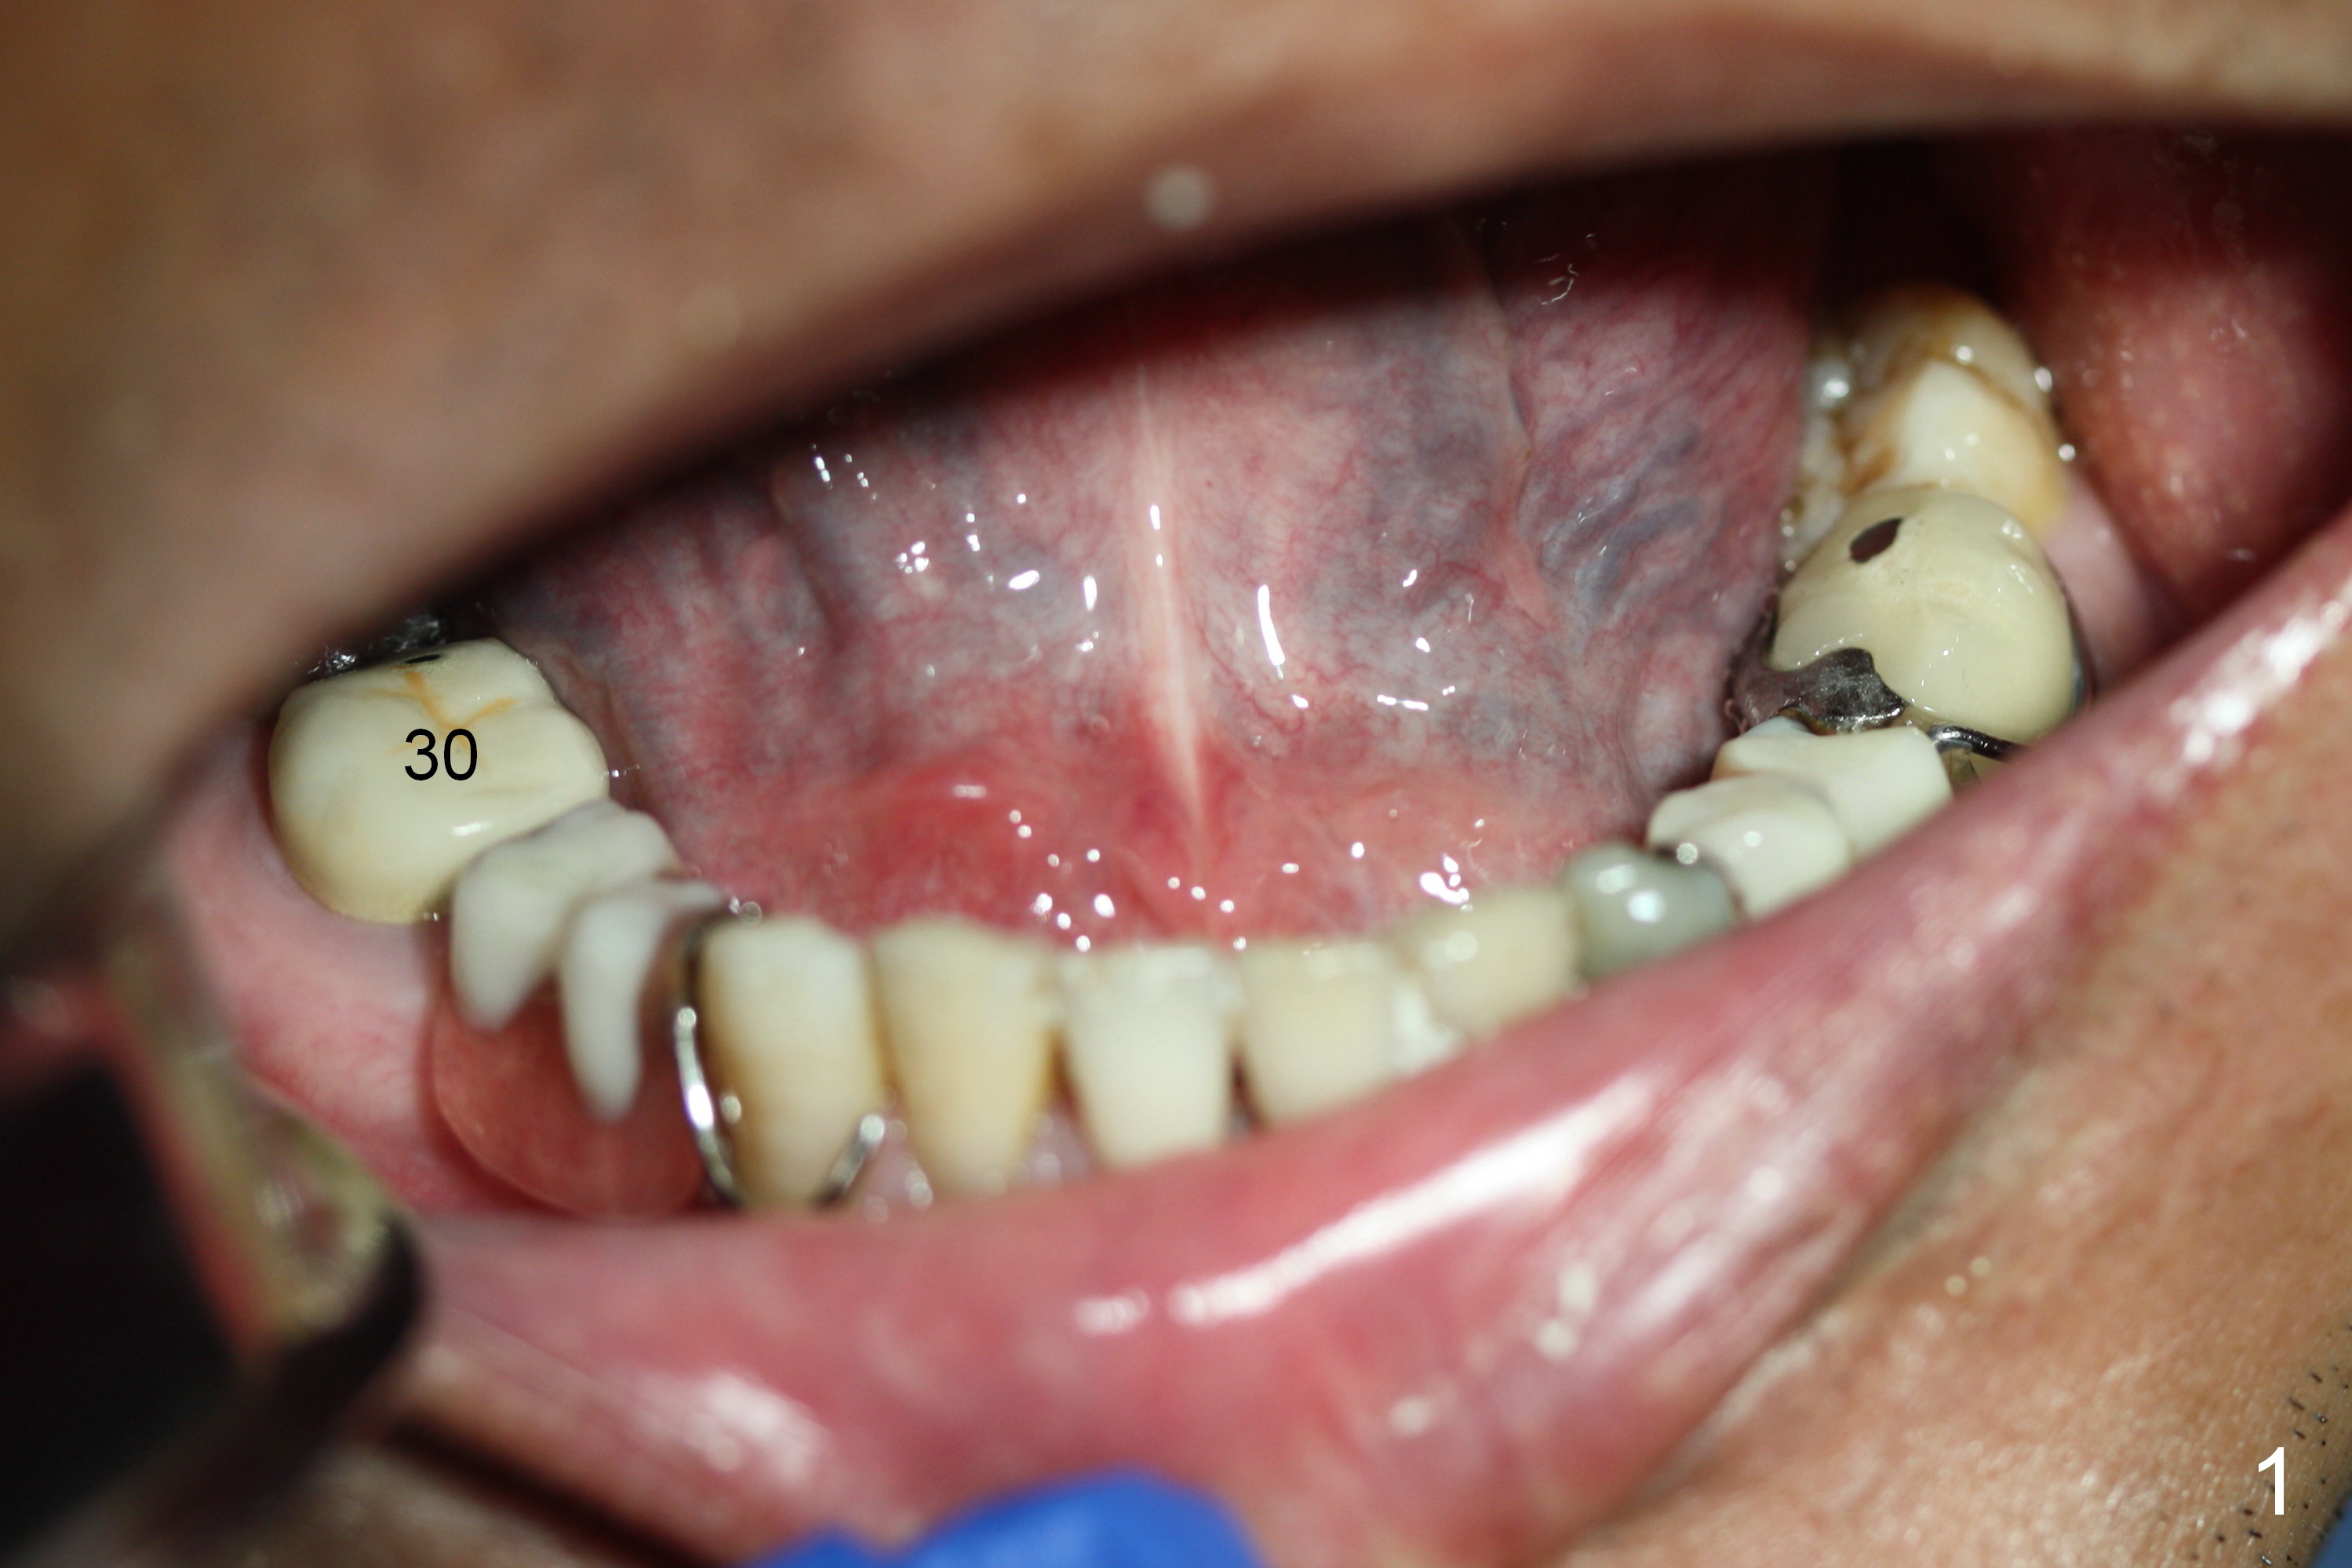

The patient has lost several teeth, which are replaced by removable partial dentures. He wants to have implants in the lower right first because of loss of a buccal clasp over the tooth #30 (Fig.1). When the lower partial is removed, a narrow soft tissue band is visible in the edentulous area. The hard tissue ridge is approximately 3 and 5 mm buccolingually at the sites of #28 and 29, respectively (Fig.3 after initial osteotomy). To place 2 adjoining implants at the same level, the treatment plan is modified: a 3 mm 1-piece implant will be placed at #28, while the plan at #29 remains the same: a 4.5 mm 2-piece implant.

The 1st intraop PA taken after initial osteotomy at the depth of 12 mm shows that the mental loop (Fig.4 red dashed line) appears to be more superior than what is expected from CBCT study; while the apical end of the osteotomy at #28 is going to be moved mesially (>), that at #29 distally (<). Both implants (3x14 and 4.5x12 mm) are placed with insertion torque 56 Ncm (Fig.5). After placement of a 5.8x4(2) mm abutment at #29, an immediate provisional is fabricated and cemented (Fig.6 P). The partial is modified and the left portion is seated (Fig.6 <). The patient is pleased with the change: from removable to fixed appliance. There is no paresthesia postop.